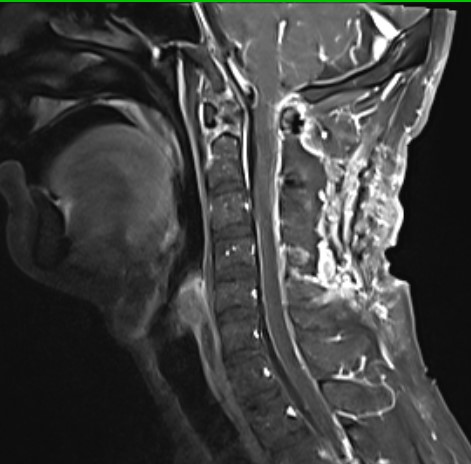

入院查头颈部MR提示C1到C2髓内占位,脊髓肿胀明显

术后MR提示肿瘤近全切除